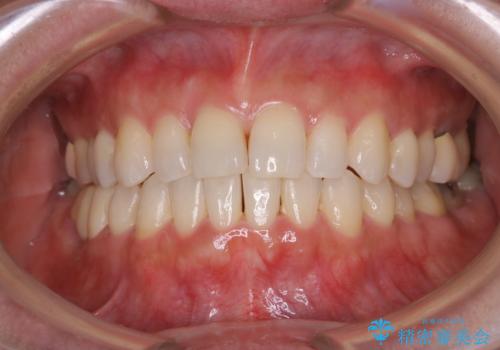

早い安いきれい!インビザラインライトで前歯のでこぼこ、反対咬合をなおす

- 前歯のがたつきと反対咬合を主訴に来院されました。

インビザライン・クリンチェック(歯のシミュレーション)を行い、

インビザラインライトで治せる範囲であることを確認し治療を開始することになりました。

今回はクリンチェックを作成したのちに、枚数が少なくても可能であることが判明したためインビザラインライトでの治療を行いました。

最初はインビザラインモデレートパッケージの予定で契約をされていたので、金額も10万円以上安くなり仕上がりも満足頂きました。